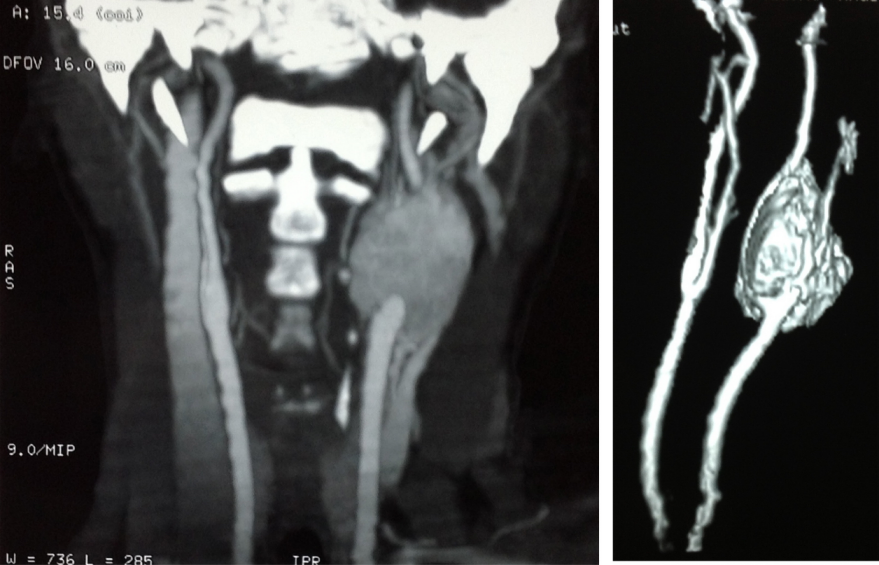

A 45-year-old female presented with a history of syncope, headache, and dyspnea for three years. A pulsatile mass was discovered on her left side of the neck. CT angiography revealed a mass located on the left carotid bifurcation classified as Shamblin II (Figure 1 [Fig. 1]). Preoperative embolization was performed the day before surgical resection. Under general anesthesia, transfemoral access was obtained with selective catheterization of internal and external carotid artery. A 5x4 cm tumor was localized at the biphurcation of the left common carotid artery with feeding vessels from the ascending pharyngeal, occipital and superior thyroid arteries. Carotid occlusion test was performed to verify adequate permeability of the circle of Willis. A 6 Fr catheter was advanced into the left common carotid artery with subsequent microcatheterization of the ascending pharyngeal artery. This was followed by embolization with Contour® Polyvynil alcohol embolization particles (Boston Scientific, Boston, MA) of 150–250 microns, and then by injection of Embospheres® (Merit Medical Systems, USA) of 300–500 microns until vessel occlusion was achieved. The same procedure was performed for the occipital artery. The superior thyroid artery could not be embolized because of severe vessel tortuosity. A post-embolization angiography revealed adequate permeability of intracranial and extracraneal vessels. An average decrease of 80% of the tumor’s blood flow was documented. After the procedure was completed, the patient woke up without neurological or visual deficits. The surgical resection was then performed under general anesthesia. A transverse cervical incision and dissection to complete exposure of the tumor was done. The surrounding vascular structures (common carotid artery, internal and external carotid) with extension to the skull base were identified. The hypoglossal nerve, the hypoglossal loop and vagus nerve, were released without severing. The tumor resection was performed with the subadventitial technique [8]. Minimum bleeding occurred and no neurovascular structures were severed.